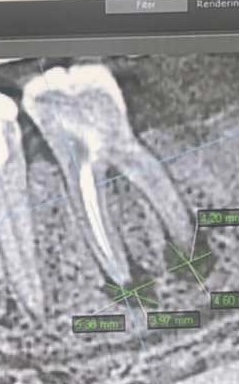

Периодонтит был на зубе под коронкой. Сначала делали резекцию корня, через три года все пошло по новой и пришлось удалить(